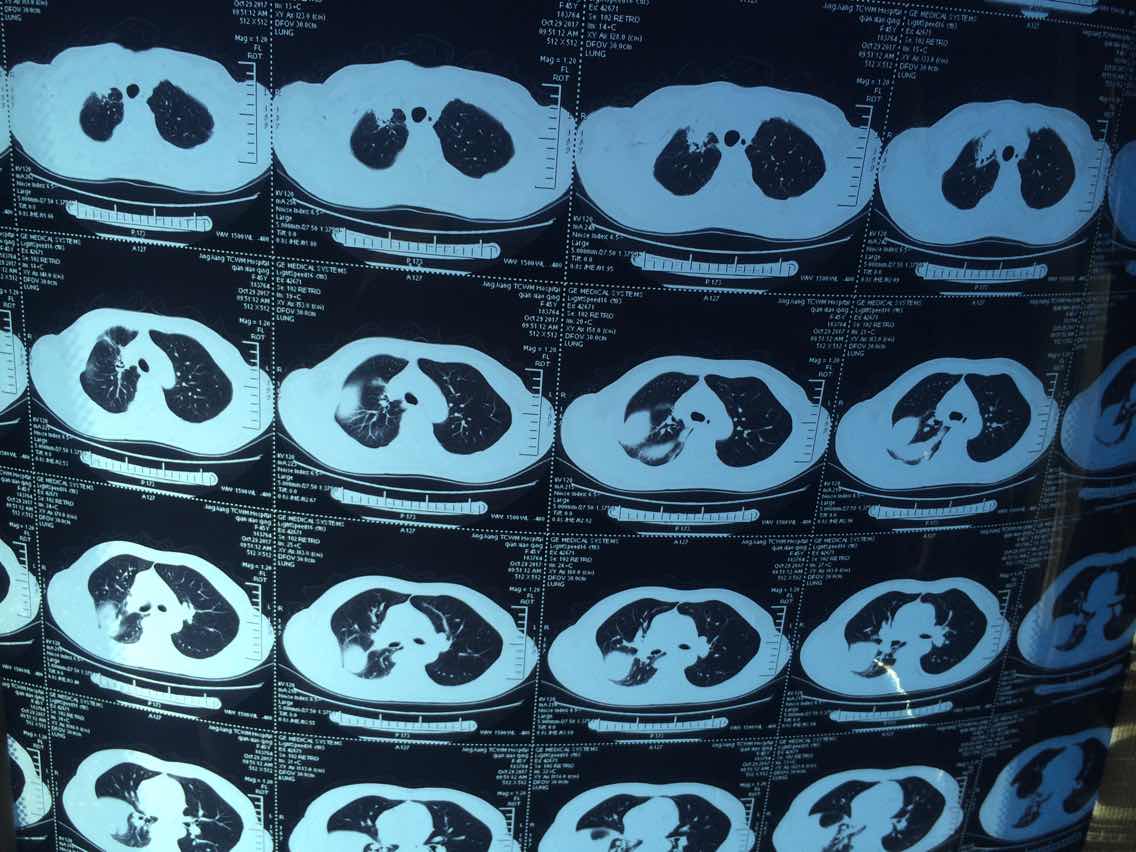

2017.10.29ct

陈医生,这是2016.10.26的ct看看拍的对不